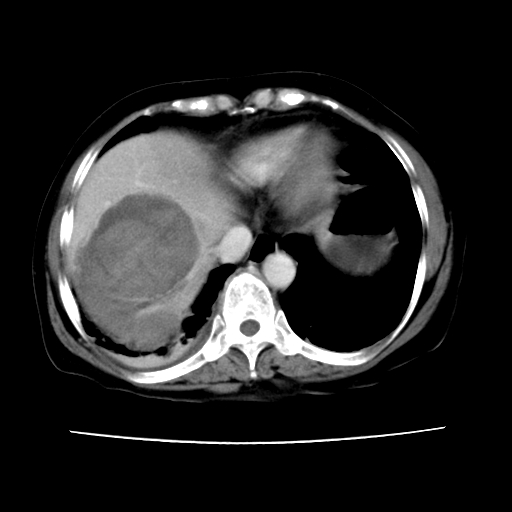

标题: CT16642:男62岁,突发性上腹部疼痛来诊。请讨论!

2008-6-10ct平扫

ct增强

6月片:肝血管瘤并破裂出血?肝左外叶囊肿

考虑肝腺瘤出血可能,肝血管瘤增强表现不是很典型,放在第二。

考虑为肝血管瘤破裂出血并肝包膜下血肿;右侧少量胸腔积液。

符合肝癌破裂出血并包膜下血肿。

6月份ct片显示肝内巨大混杂密度团块,伴包膜下积液(内含液液平面),增强多无明显强化。只能考虑肝占位病变,并肝内、血膜下血肿。肝ca并出血多见,而肝血管瘤并破裂出血少见。